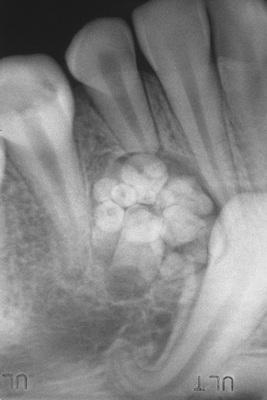

A calcified mass with the radiodensity of tooth structure, overlying the crown of the mandibular right second molar.

complex odontoma

Surgical specimen consisting of more than 20 malformed toothlike structures.

compound odontoma

This decalcified section shows a disorganized mass of dentin intermixed with small pools of enamel matrix.